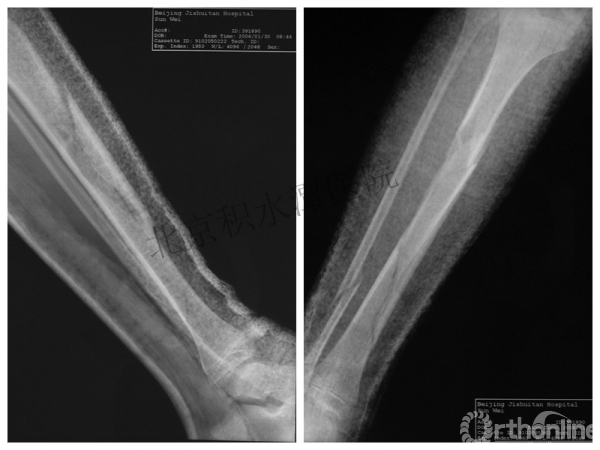

病例分享四

女孩、8岁,桡骨远端骨折

原始损伤

伤后1个月

伤后14个月